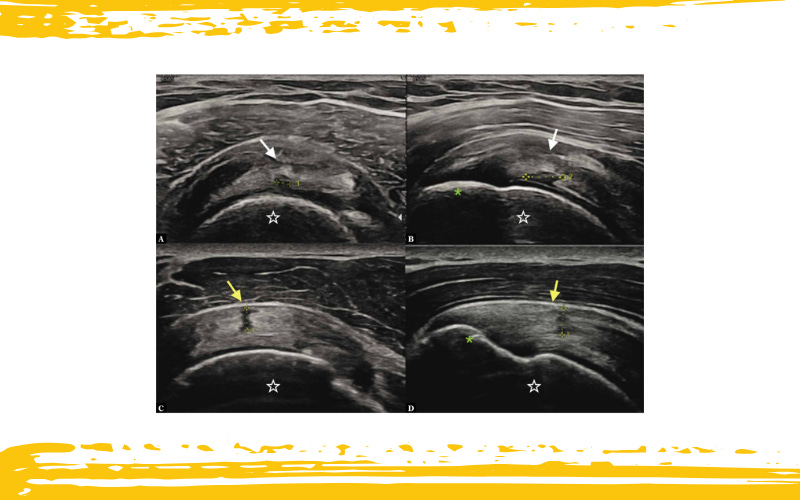

Rotura parcial del tendón del supraespinoso.

Rotura de la superficie articular (flechas blancas) en los cortes en eje corto (A) y eje largo (B), y rotura de la superficie bursal (flechas amarillas) en los cortes en eje corto (C) y eje largo (D).

La rotura se visualiza como un área hipoecoica con pérdida del patrón fibrilar normal, que afecta únicamente a una de las caras del tendón.

Estrella: cabeza humeral.

Asterisco: tubérculo mayor en la huella del supraespinoso.